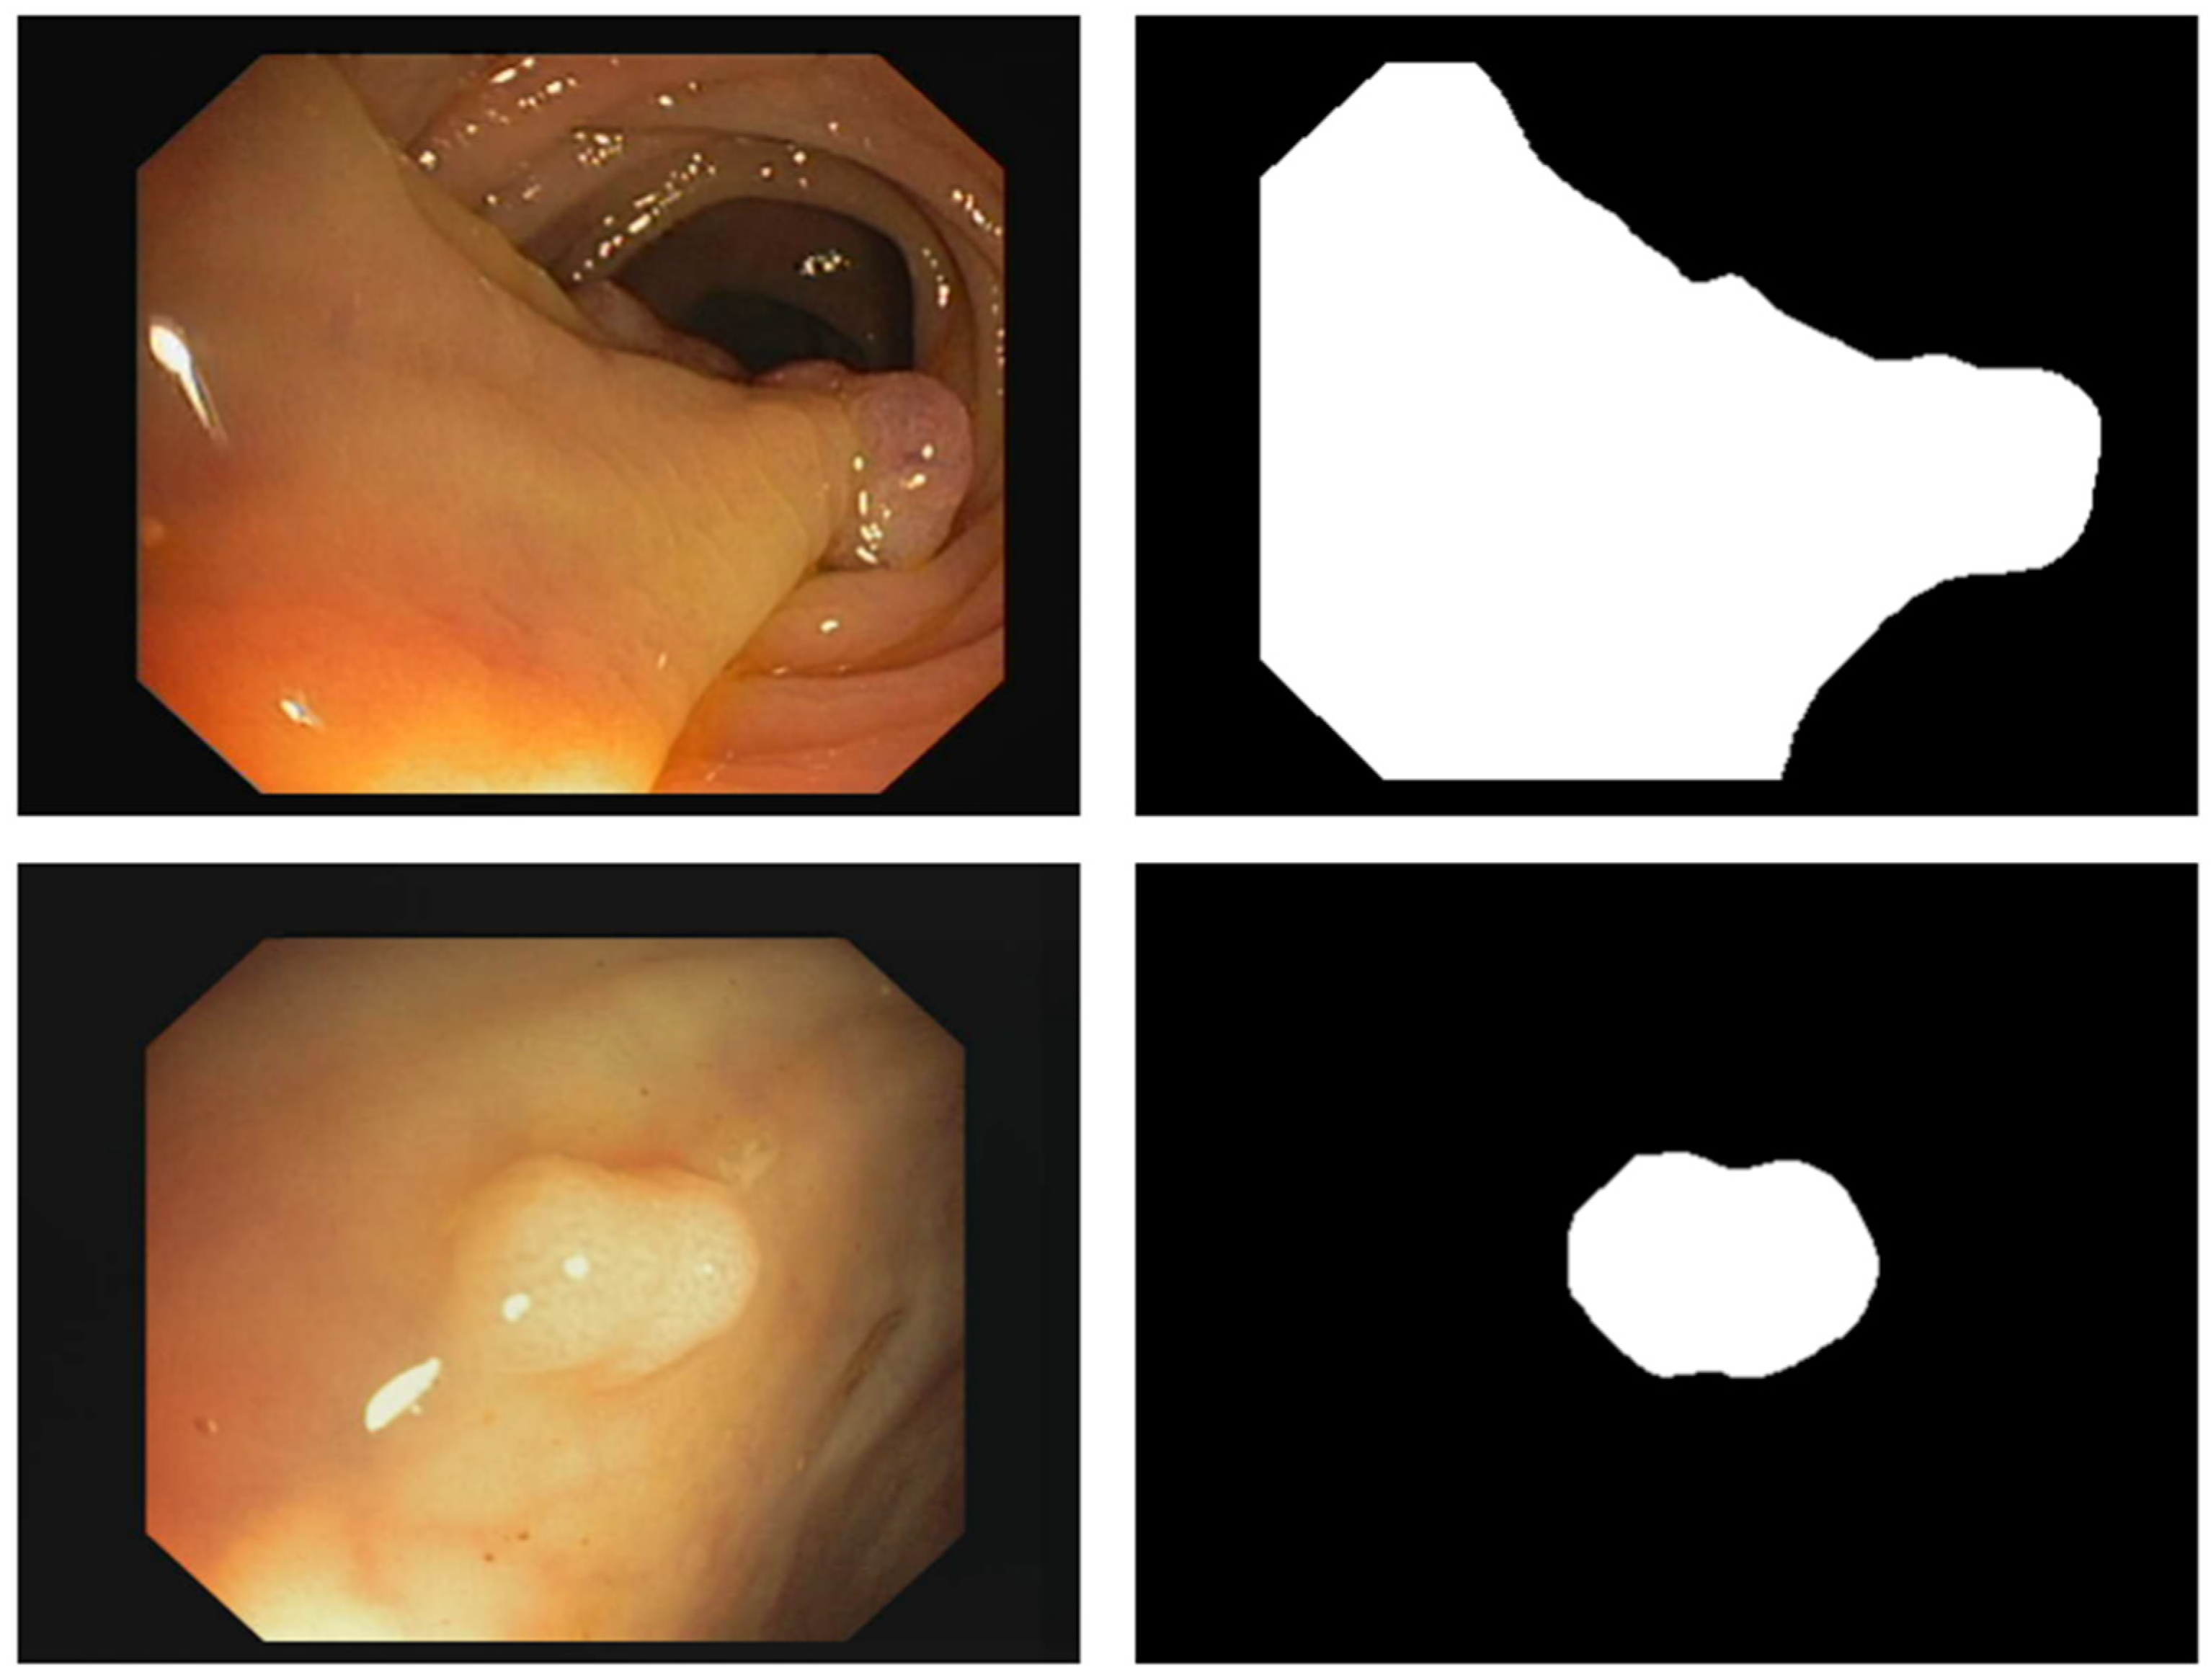

- PUTS: A novel Swin-Unet transformer-based polyp segmentation model;

3.2. PUTS: Vision Transformer-Based Polyp Segmentation

3.2.1. Motivation

3.2.2. PUTS Architecture

4.2. Polyp Segmentation Performance Results